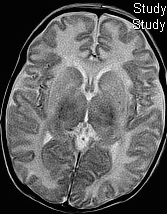

Hypoxic-ischaemic injury to gray matter (thalami and lentiform nuclei) demonstrates characteristic T1 hyperintensity and T2 hypointensity

Neonatal hypoxic-ischaemic encephalopathy (HIE) is the result of a global hypoxic-ischaemic brain injury in a term neonate, usually after asphyxia.

Radiographic features

In term infants blood flow is ventriculofugal and changes are mainly, like in older children, in watershed-border zones; namely, parasagittal grey matter and subcortical white matter. Profound HIE in term babies results in thalamic and basal ganglia as well as sensorimotor cortex (perirolandic region) injury.

MRI

MRI is the most sensitive and specific imaging technique for examining infants with suspected hypoxic-ischaemic brain injury. Conventional sequences can help exclude other causes of encephalopathy such as haemorrhage, cerebral infarction, neoplasms, or congenital malformations.

A number of patterns of injury are encountered (see patterns of neonatal hypoxic-ischaemic brain injury) depending on the stage of brain maturation and severity of asphyxia, with the following expected signal intensity changes:

T1

grey matter: hyperintense

white matter: hypointense

T2

grey matter: variable depending on the time of imaging and presence of haemorrhage

white matter: hyperintense